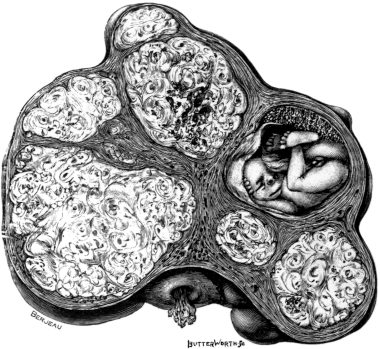

| 1. | Secondary Cancer of the Ovary | 15 |

| 2. | Secondary Cancer of the Ovary in Section | 15 |